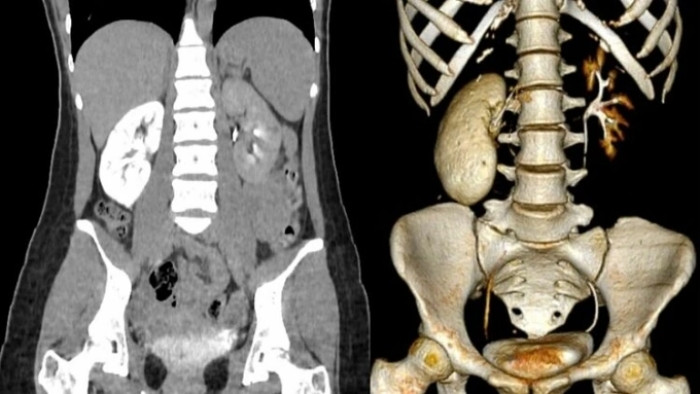

Thận bệnh nhân 18 tuổi gần như "hóa đá". (Ảnh: BSCC)